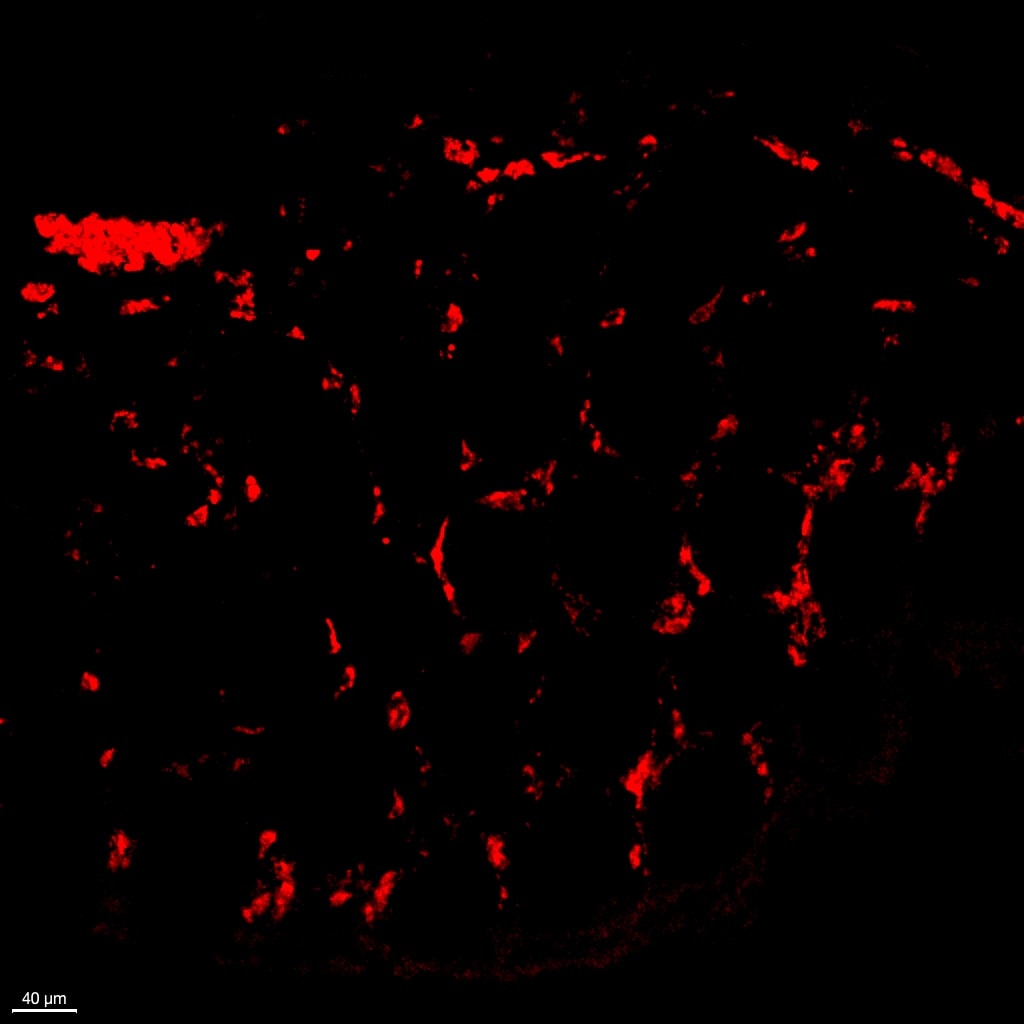

Name: Anonymous

Application: Immunocytochemistry/Immunofluorescence

Sample Tested: Colon tissue

Species: Primate

Verified Customer | Posted 04/09/2025

Human CCR9 PE‑conjugated Antibody FAB179P